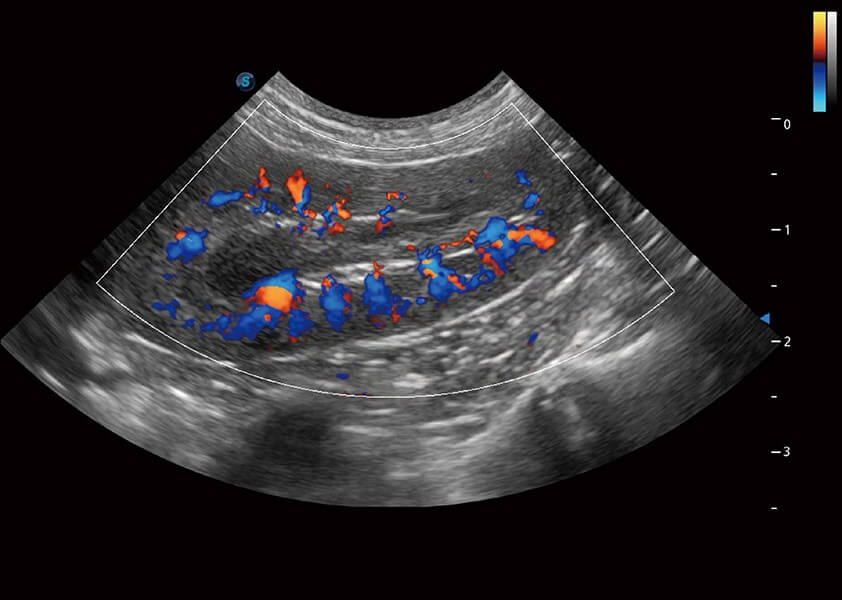

ProPet 60 作为一款高端台式动物超声设备,为动物医生的日常诊断提供了一系列贴合动物临床需求、解决临床实际问题的高级成像功能。凭借全系列高清探头,满足医生对腹部、心脏、生殖、浅表、肌骨等成像的所有需求,切实帮助您提升检查效率,提高诊断信心。

动物是人类最亲密的朋友和最值得信赖的伙伴。玖鼎集团也一直致力于探索动物专用的超声影像解决方案。 全新推出的ProPet系列,是玖鼎集团在动物超声影像智能化、专业化、精准化的一次跨越式革新。动物不能用言语来表述自己的不适,通过超声影像,ProPet系列搭建了动物医生与不同物种沟通的“桥梁”,为动物医生注入了“治愈之力”。